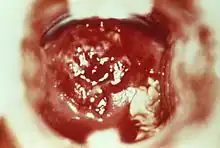

| HSV cervicitis | |

- ↑ Image by Mikael Häggström, MD. Reference for findings: Ali Ismail, M.B.B.S., Ziyan T. Salih, M.D. "Chronic cervicitis". Pathology Outlines.